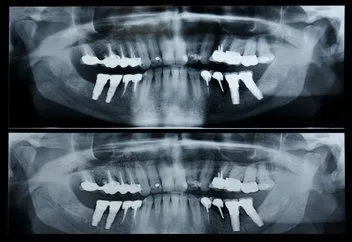

Panorex A panorex is a very impressive piece of imaging machinery in that it is capable of identifying many issues and structures that a normal x-ray is not. Initially you will sit in a chair or stand with your chin on a small ledge. Once positioned in the machine, it will rotate around your entire head taking a full 360 degree view of the teeth, head, sinuses and bones.

The ability to view the full structure of your head as a whole is very informative to the dentist. It will allow us to see any potential problems and make sure that everything is functioning as it should be. The panorex is capable of viewing specific types of structural problems, infections or asymmetry among many others.